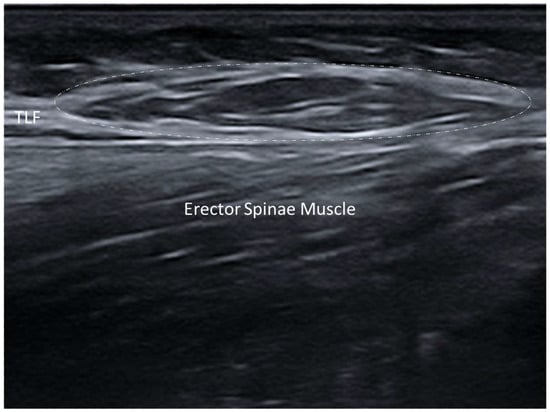

3.5.3. Myofascial Trigger Points